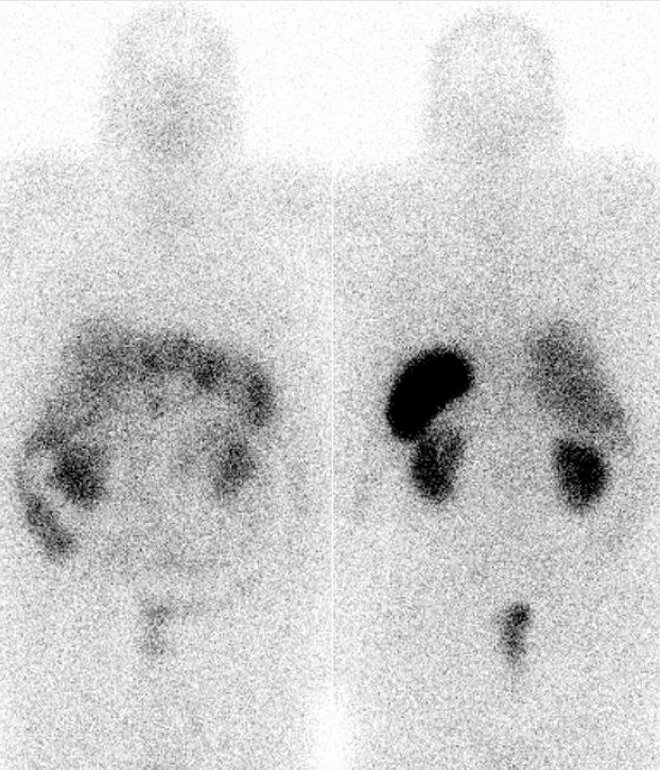

Po příslušné přípravě jsme po i.v. podání 150 MBq analogu somatostatinu značeného

111In (přípravek OctreoScan firmy Mallinckrodt Medical) na dvouhlavé tomografické kameře E.CAM firmy Siemens za 4 hodiny provedli planární celotělovou scintigrafii

(obr. 1), za 24 hod. pak opět celotělovou scintigrafii (obr. 2) a cílenou tomografickou scintigrafii břicha

/ Obr. č. 1: Celotělová scintigrafie v přední a zadní projekci 4 hod. po aplikaci OctreoScanu.

/ Obr. č. 2: Celotělová scintigrafie v přední a zadní projekci 24 hod. po aplikaci OctreoScanu.

Na všech těchto scintigramech je patrná jednak fyziologická difuzní depozice radioaktivity v játrech, slezině, ledvinách, močovém měchýři, střevech. V játrech jsou vícečetná patologická ložiska. Také zjištěna další dvě ložiska: jedno pod levým jaterním lalokem těsně vpravo od střední čáry, další ložisko níže mezi ledvinami těsně vlevo od střední čáry. Nález odpovídá mnohočetným metastázám karcinoidu v játrech, dvě ložiska pod levým lalokem jaterním a v mesogastriu mohou být primárními nádorovými lézemi nejspíše v ileu.